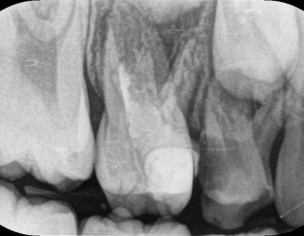

My daughter is 7 and hav deep cavity I took her to dentist one said she need 1 extraction and when I went to pediatric dentist she said she needs 4 extractions which she is going to do altogether same day I am attaching her xrays can any dentist plz advise after looking at the xrays thanks

Her both upper D are definitely for extraction and for her E need to evaluate clinically as well there might get b some Endodontic treatment and space maintainers afterwards

After extraction she will need space maintainer to keep first molar in its place so better to go for RCT to keep this tooth till age 12